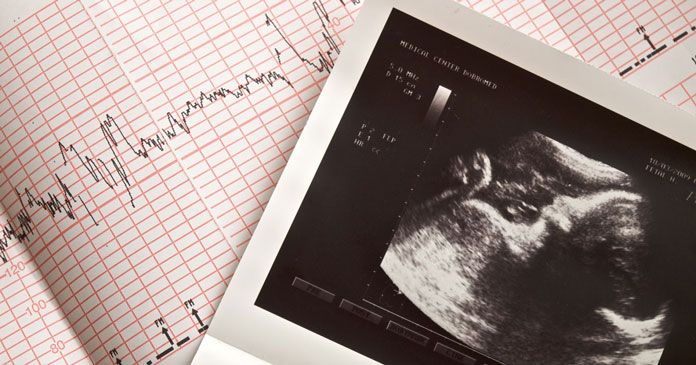

Drengebørn vokser hurtigere i livmoderen og har derfor et større behov for næringsstoffer og ilt, end moderkagen umiddelbart kan diske op med. Det kan være en af årsagerne til nogle af de graviditetsrelaterede komplikationer, som opstår.

Hver tiende kvinde oplever problemer som hæmmet fostertilvækst og præeklampsi, som er en tilstand med forhøjet blodtryk og kramper, der kan være livstruende for såvel moderen som hendes ufødte barn.

Her forklarede forskerne, at netop fordi drengefostre vokser hurtigere i livmoderen og kræver flere næringsstoffer og mere ilt end pigefostre, er deres risiko for underernæring større. Udover at hæmme drengenes vækst og mindske deres fødselsvægt øger det deres risiko for at udvikle hjerte-kar-sygdomme senere i livet.

Hvordan et foster vokser og udvikler sig, afhænger af hvor godt moderkagen fungerer.

Moderkagen indeholder tusindvis af små kraftværker – eller mitokondrier – som omdanner fedt, kulhydrat og protein til energi. Forskere har observeret, at moderkagen arter sig forskelligt, afhængig om fostret er han- eller hunkøn.